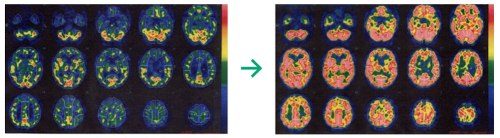

脳の血流変化

体表の血流変化